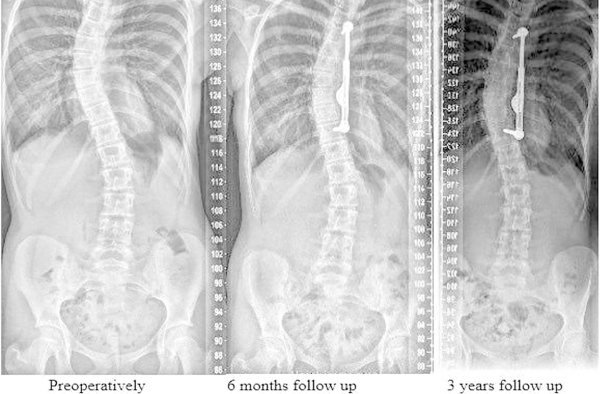

El propósito del presente estudio fue evaluar la eficacia de un dispositivo auto-distractor periapical posterior (ApiFix) aprobado recientemente por la Administración de Drogas y Alimentos de los Estados Unidos (FDA) que está diseñado para corregir gradualmente la deformidad sin fusión espinal.

El uso de la varilla de trinquete auto-distraída cóncava periapical unilateral inicialmente se asoció con resultados clínicos y radiográficos prometedores.

Sin embargo, no se observó distracción y la alta tasa de eventos adversos graves en 2 años se consideró inaceptable para la aplicación clínica adicional de este dispositivo en nuestra institución, a pesar de la reciente aprobación de la FDA.